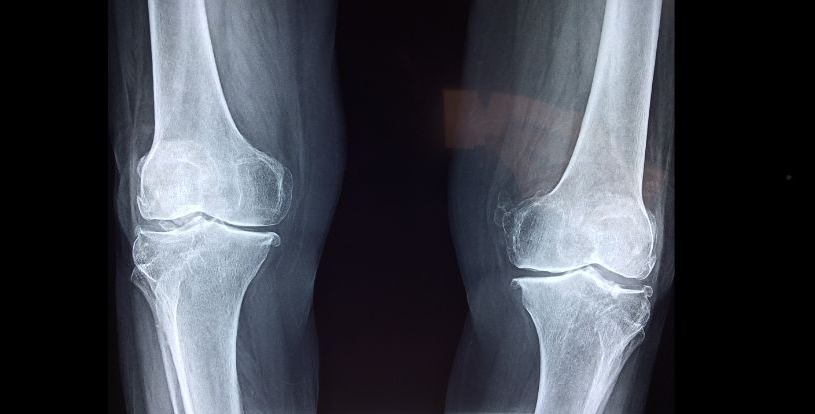

Остеопороз – це захворювання кісток, яке характеризується зменшенням щільності та міцності кісткової тканини, що призводить до крихких і ламких кісток. Це збільшує ризик переломів, особливо хребта, стегон та зап’ясть.

Хоча ранні симптоми можуть бути непомітними, певні ознаки вказують на ослаблення кісток. Найсерйозніші ускладнення остеопорозу — це переломи, які можуть спричинити хронічний біль, госпіталізацію, інвалідність, депресію, зниження якості життя та підвищення смертності.